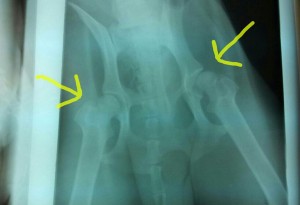

—-X-RAY UPDATE—-

Samuel had his x-rays done today (2/3/14) along with his neuter. As you can see on the right side the femoral head is sitting slightly outside of his pelvic bone (ball and socket joint). The patellas (kneecap) on both of his hind legs are also bad Ibshawāy .

The good news is that Samuel is not in any discomfort although he walks a little different than the other dogs. Also, Dr. Hedrick does not think that he needs surgery at this current time. As Samuel gets healthier he will regain his muscle mass in his hind quarters and this will hopefully help hold all of his joints in place. If it doesn’t then major surgery will be in his future. Please keep him in your thoughts.